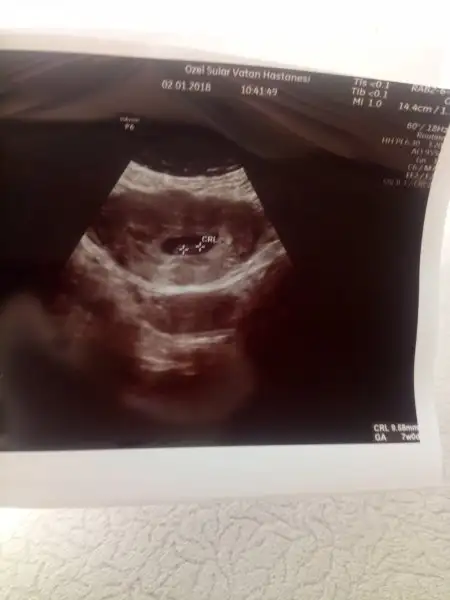

Ama minisimiz iyi çok şükür maşallah BarekAllah gelişimi de iyi dedi ikili test için de 2 hafta sonra cagrdi cinsiyet için belli olabilir falan demedi ama gerçi bizde sormadık